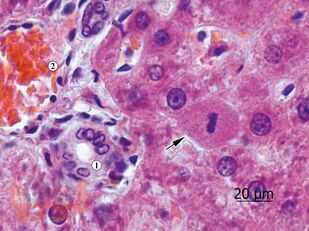

Учебное пособие выполнено в формате, удобном для изучения гистологии русско- и англоязычными студентами медицинских вузов. Все тексты даны на двух языках в сжатом объёме, но без потери сведений, имеющих принципиальное значение. В пособии представлены все основные разделы изучаемого предмета – гистологическая техника, цитология, общая и частная гистология, эмбриология человека. Издание иллюстрировано оригинальными микрофотографиями, сделанными авторами с микропрепаратов, изготовленных в ЗАО "Ретиноиды". Подрисуночные подписи и обозначения выполнены также на двух языках.